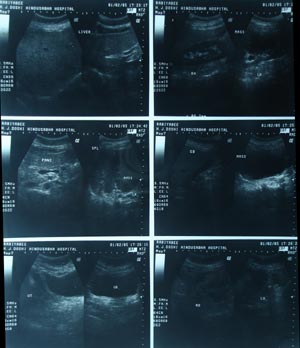

Ultrasonography for medicosurgical indication

The routine USG for medicosurgical purpose is done in a systemic way of performance. Unless and until, specified about target organ the sonographer usually include all the structures of the abdomen. Start with liver in all planes, kidney in short & long axis, spleen, pancreas, vessels, particularly IVC & Aorta with any visible LN in any group. Bladder has to be full for evaluation of genitourinary tract.